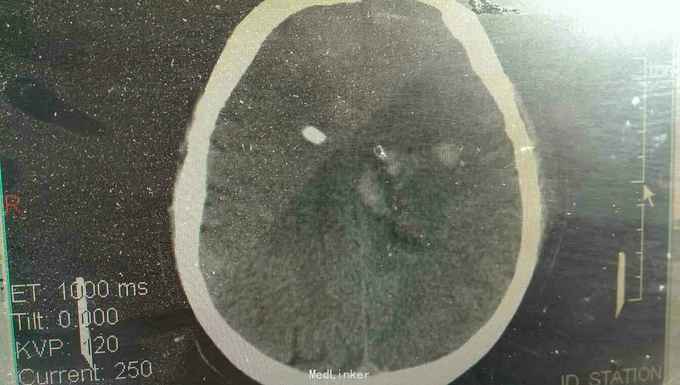

患者男性,56岁。以突发头痛伴意识不清半小时入院。患者入院半小时前突然自觉头痛,性质剧烈,呕吐多次,随即意识不清。来我院就诊。

浅昏迷状态,无语言。刺激后右侧肢体不动,左侧肢体可动。双侧瞳孔等大正圆,直径3.0毫米,光反射迟钝。右侧病理反射阳性。

脑出血,高血压病 急诊行微创硬通道内镜下血肿清除术,术中清除大部分血肿,患者术后第二天清醒右侧肢体三级,语言迟缓。